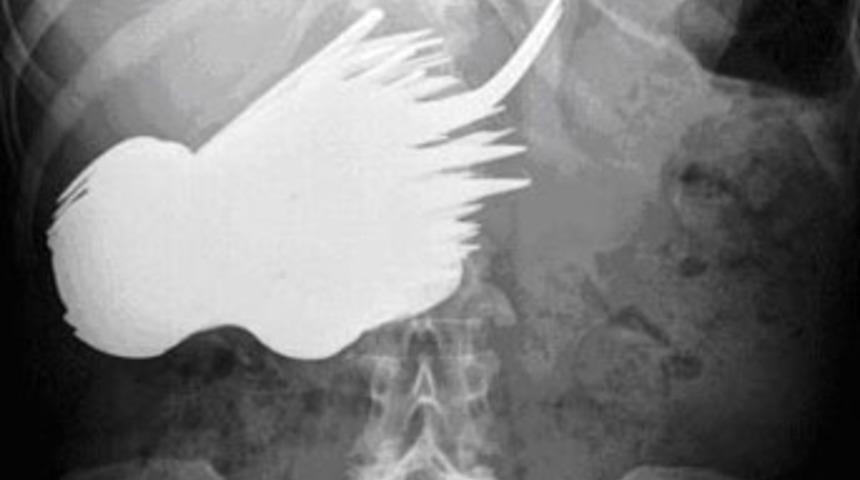

Hollanda'da karnı ağrıdığı için hastaneye giden bir kadının midesinden 78 parça çatal-kaşık çıkarıldı.

Margaret Daalman'ın (52) röntgen filmini çeken doktorlar şoke oldu. Daalman'ın vücudunun çeşitli yerlerine sıkışmış çatal ve kaşıklar ameliyatla alındı. Kadının psikiyatrik bir rahatsızlığı olduğu, masaya oturduğunda yemek yerine çatal ve kaşıkları yediği belirtildi.